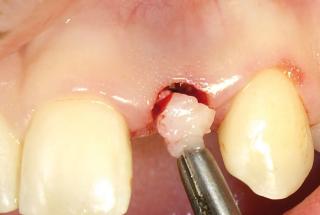

Clinical cases

MPI closely monitors clinical cases in the market to ensure their correct functioning and successful outcome.